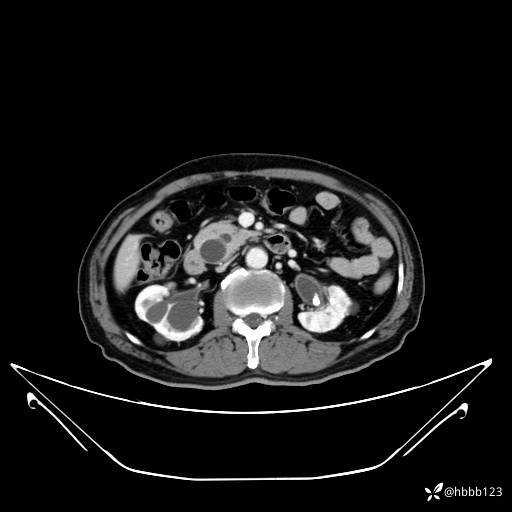

动脉期: